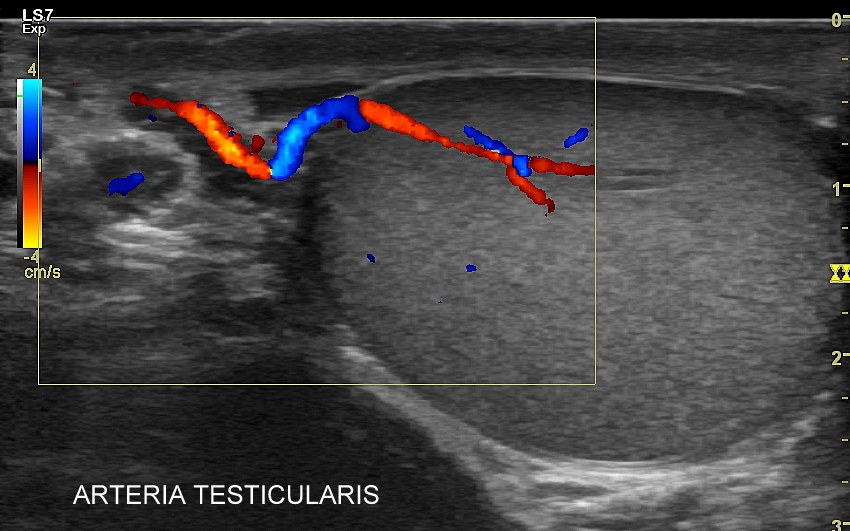

USG moszny i kanału pachwinowego jest podstawową metodą obrazowania jąder, najądrzy, powrózka nasiennego, w tym nasieniowodu oraz towarzyszących im naczyń żylnych i tętniczych. Badanie USG przeprowadzić należy w przypadku wystąpienia bólu i obrzęku jąder, pojawienia się macalnego guzka w obrębie moszny, podejrzenia skrętu lub zapalenia jądra, żylaków powrózka nasiennego, w ramach oceny dojrzewania płciowego chłopców. Kanał pachwinowy bada się także w sytuacji podejrzenia wnętrostwa, przepukliny pachwinowej, w celu oceny węzłów chłonnych, a także nasieniowodu w diagnostyce niepłodności męskiej.

Mosznę bada się aparatem USG wyposażonym w dedykowaną sondę o wysokiej rozdzielczości przeznaczoną do oceny jąder i drobnych struktur moszny, koniecznie z zastosowaniem trybów dopplerowskich, takich jak Doppler kodowany kolorem, Doppler spektralny i obrazowanie mikrounaczynienia. Dopełnieniem badania USG jąder jest użycie w stosownych przypadkach trybu elastografii oraz trybu USG z kontrastem (CEUS). Lekarzem, który pierwszy we Wrocławiu i na Dolnym Śląsku przeprowadził badanie CEUS jąder jest dr Tomasz Szczepański.